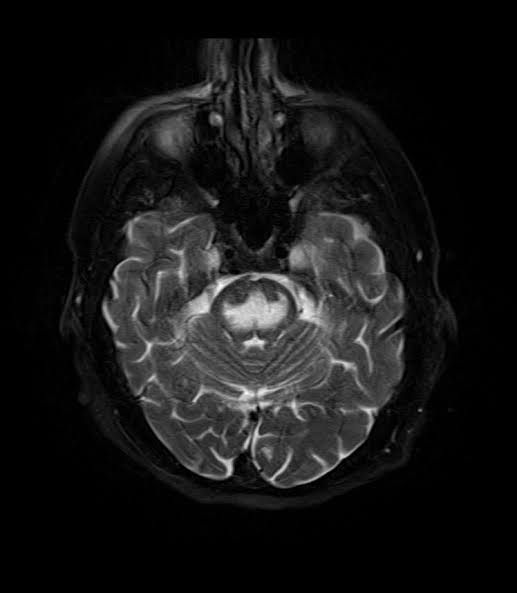

The given image is a T2 weighted MRI scan of the brain which shows hyperintensity in the pons secondary to pontine myelinosis. This is most often an iatrogen condition resulting from rapid correction of hyponatremia. The pathophysiology behind the condition is as follows. During states of hyponatremia, the brain cells adapt to decrease intracellular osmolality so the cells still remain isotonic to the extracellular environment. If blood levels of sodium rapidly increase, the ECF becomes hypertonic without allowing brain cells sufficient time to adapt. This leads to osmotic imbalance and cells continue to lose water and are unable to function. https://en.m.wikipedia.org/wiki/Central_pontine_myelinolysis